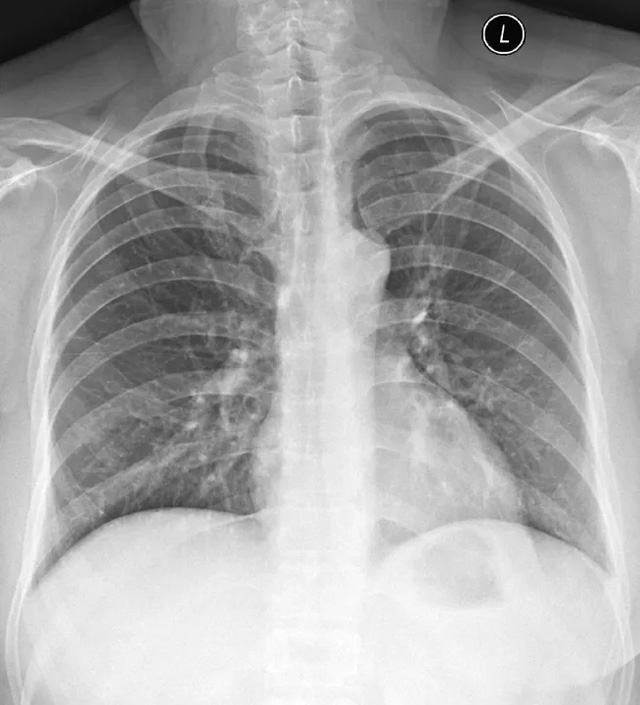

X線定位真空輔助旋切術(shù)是對臨床觸診和B超檢查均為陰性而X線片顯示的微小病變在X線立體定位引導(dǎo)下,將真空旋切刀置入乳腺可疑病灶區(qū)進(jìn)行旋切及組織病理學(xué)檢查的一種乳腺微創(chuàng)新技術(shù)。